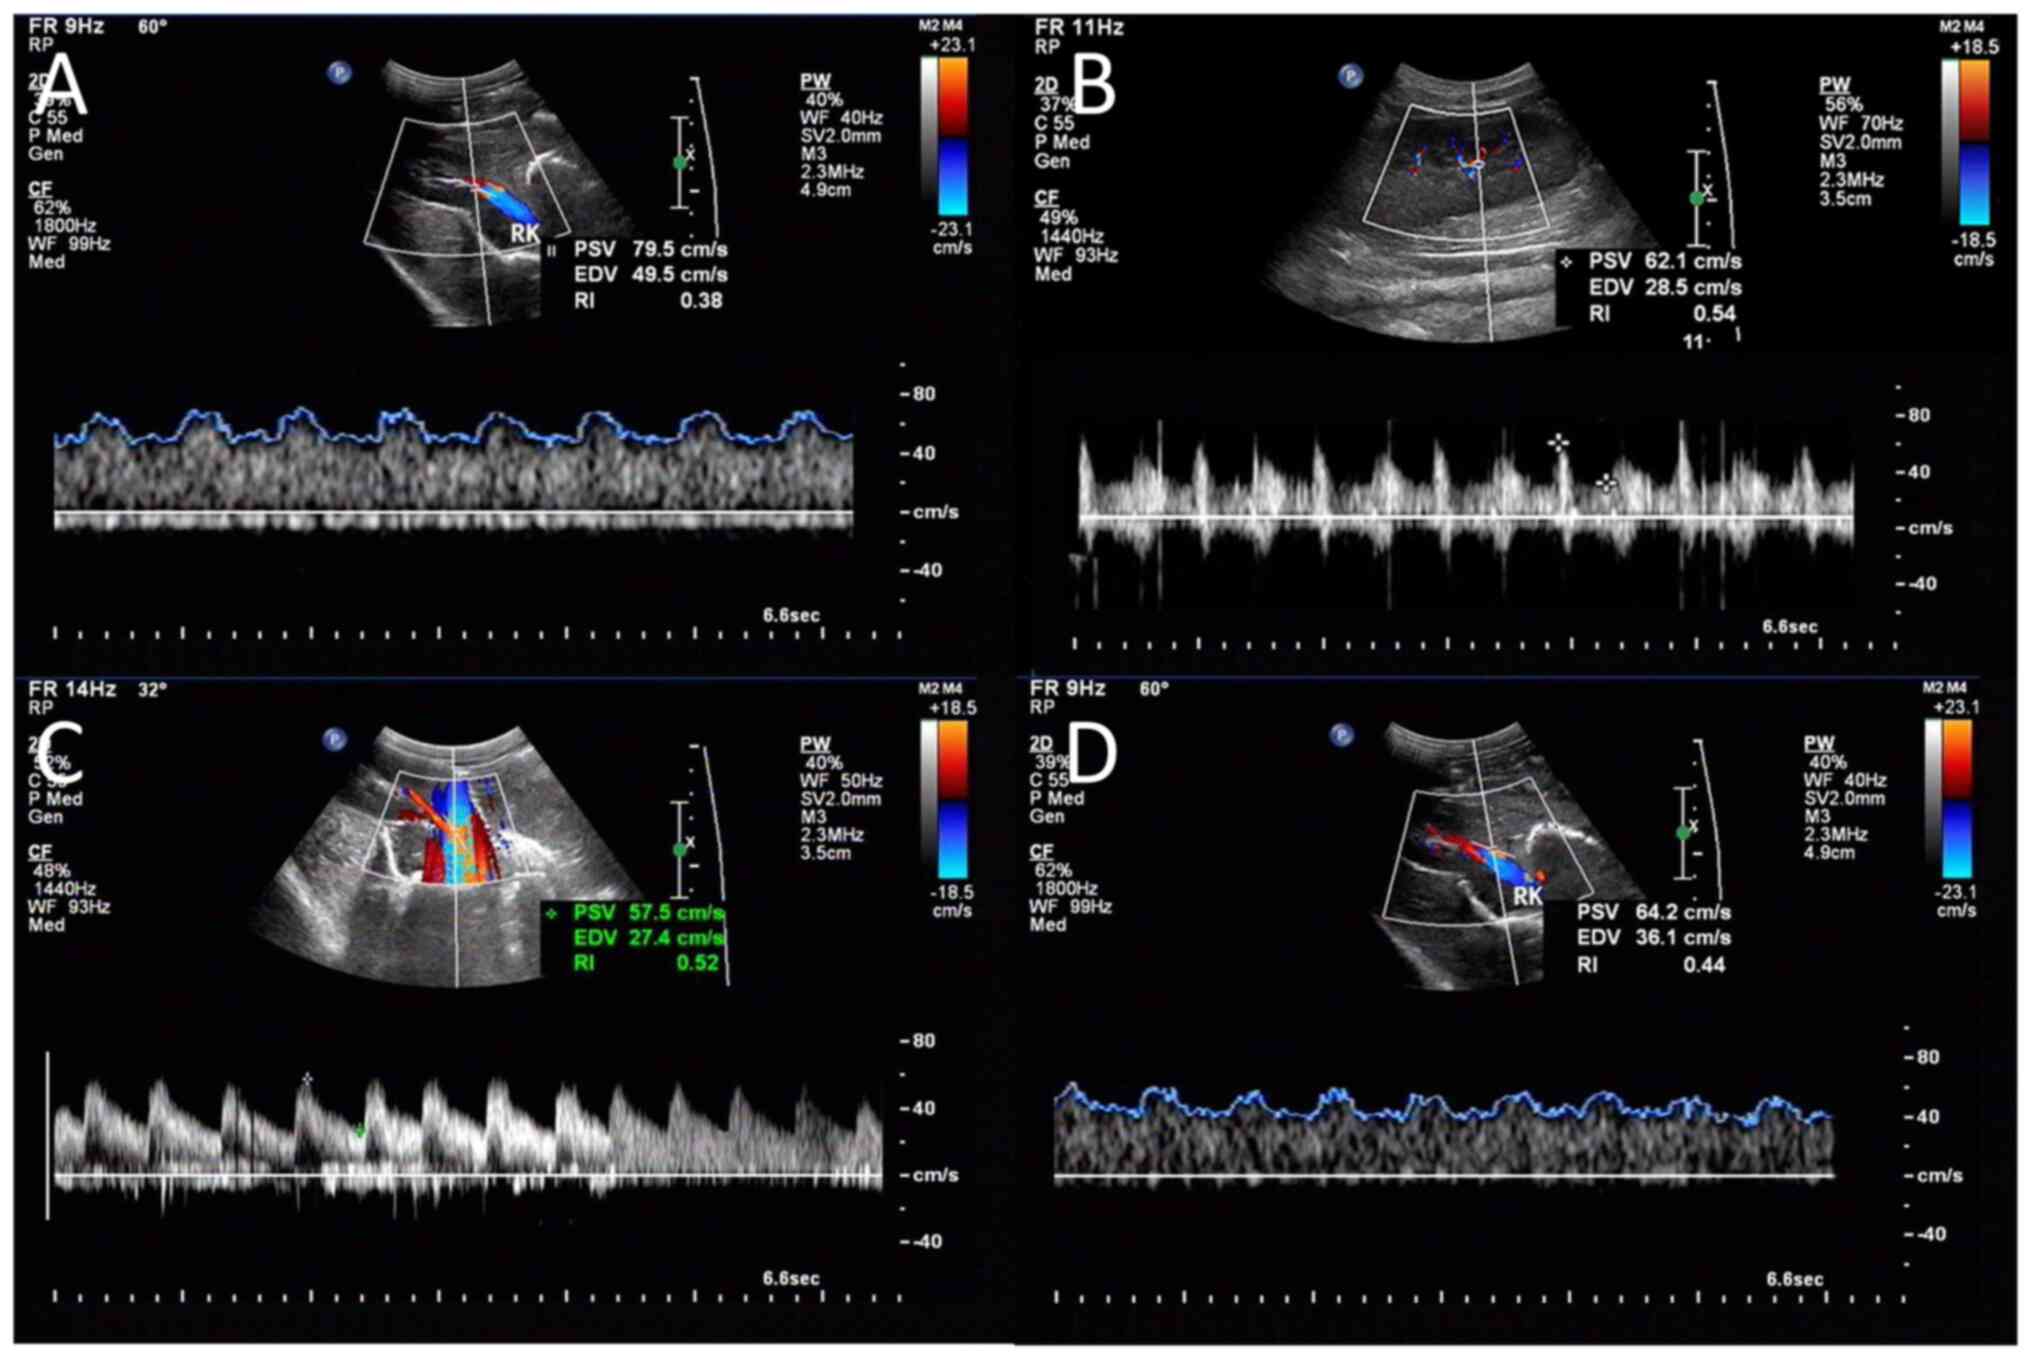

CDFI and CEUS were performed on the right kidney at the baseline and the end of the protocol (24 h) by an experienced ultrasound physician who was blinded to the study, using an ultrasound system (Aplio 500 TUS-A500; Canon Medical Systems Corporation). The probe was put on the right side of the animal's abdomen to obtain a clear image of the right kidney. An interlobar or arcuate artery was selected to obtain result from the measurement. The spectrum was considered optimal when ≥ three similar consecutive waveforms were visualized (Fig. 2A-D). The corrected resistive index (cRI) was calculated using the following equations (3). Three measurements were performed and averaged to obtain the mean cRI value. RI=(peak systolic velocity-minimum diastolic velocity)/peak systolic velocity. cRI=[observed RI -0.0026 x (80-observed HR)].

Figure 2

Representative color Doppler flow and contrast enhanced ultrasound images. Doppler gain was set in order to obtain a clear outline of flow waves with minimal background noise. An interlobar or arcuate artery was selected and the results were displayed automatically on the screen. (A) SH group. (B) SS group. (C) VAN group. (D) UTI group. SH, sham group; SS, septic shock group; VAN, vancomycin group; UTI, the ulinastatin group; ROI, region of interest.